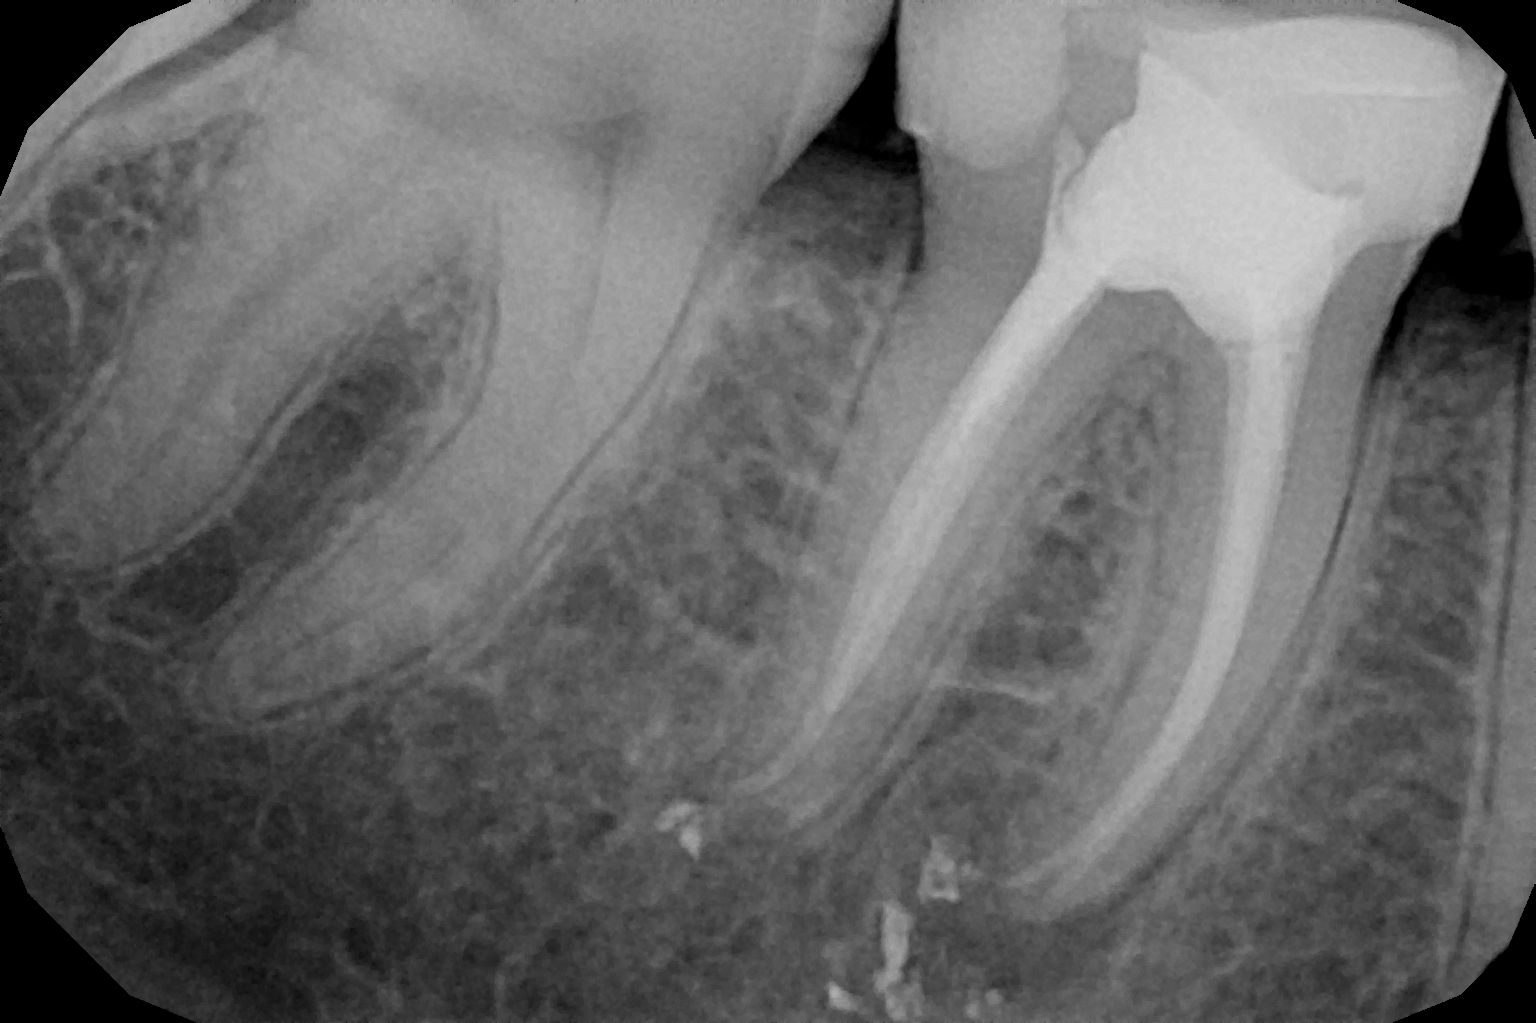

Eliminamos el tejido infectado y limpiamos los conductos.

Sellamos los conductos para evitar futuras infecciones.

Reconstruimos el diente y, si es necesario, colocamos una corona.

Es un tratamiento que elimina el nervio dañado de un diente, limpiando y sellando el interior para evitar infecciones y conservar la pieza.